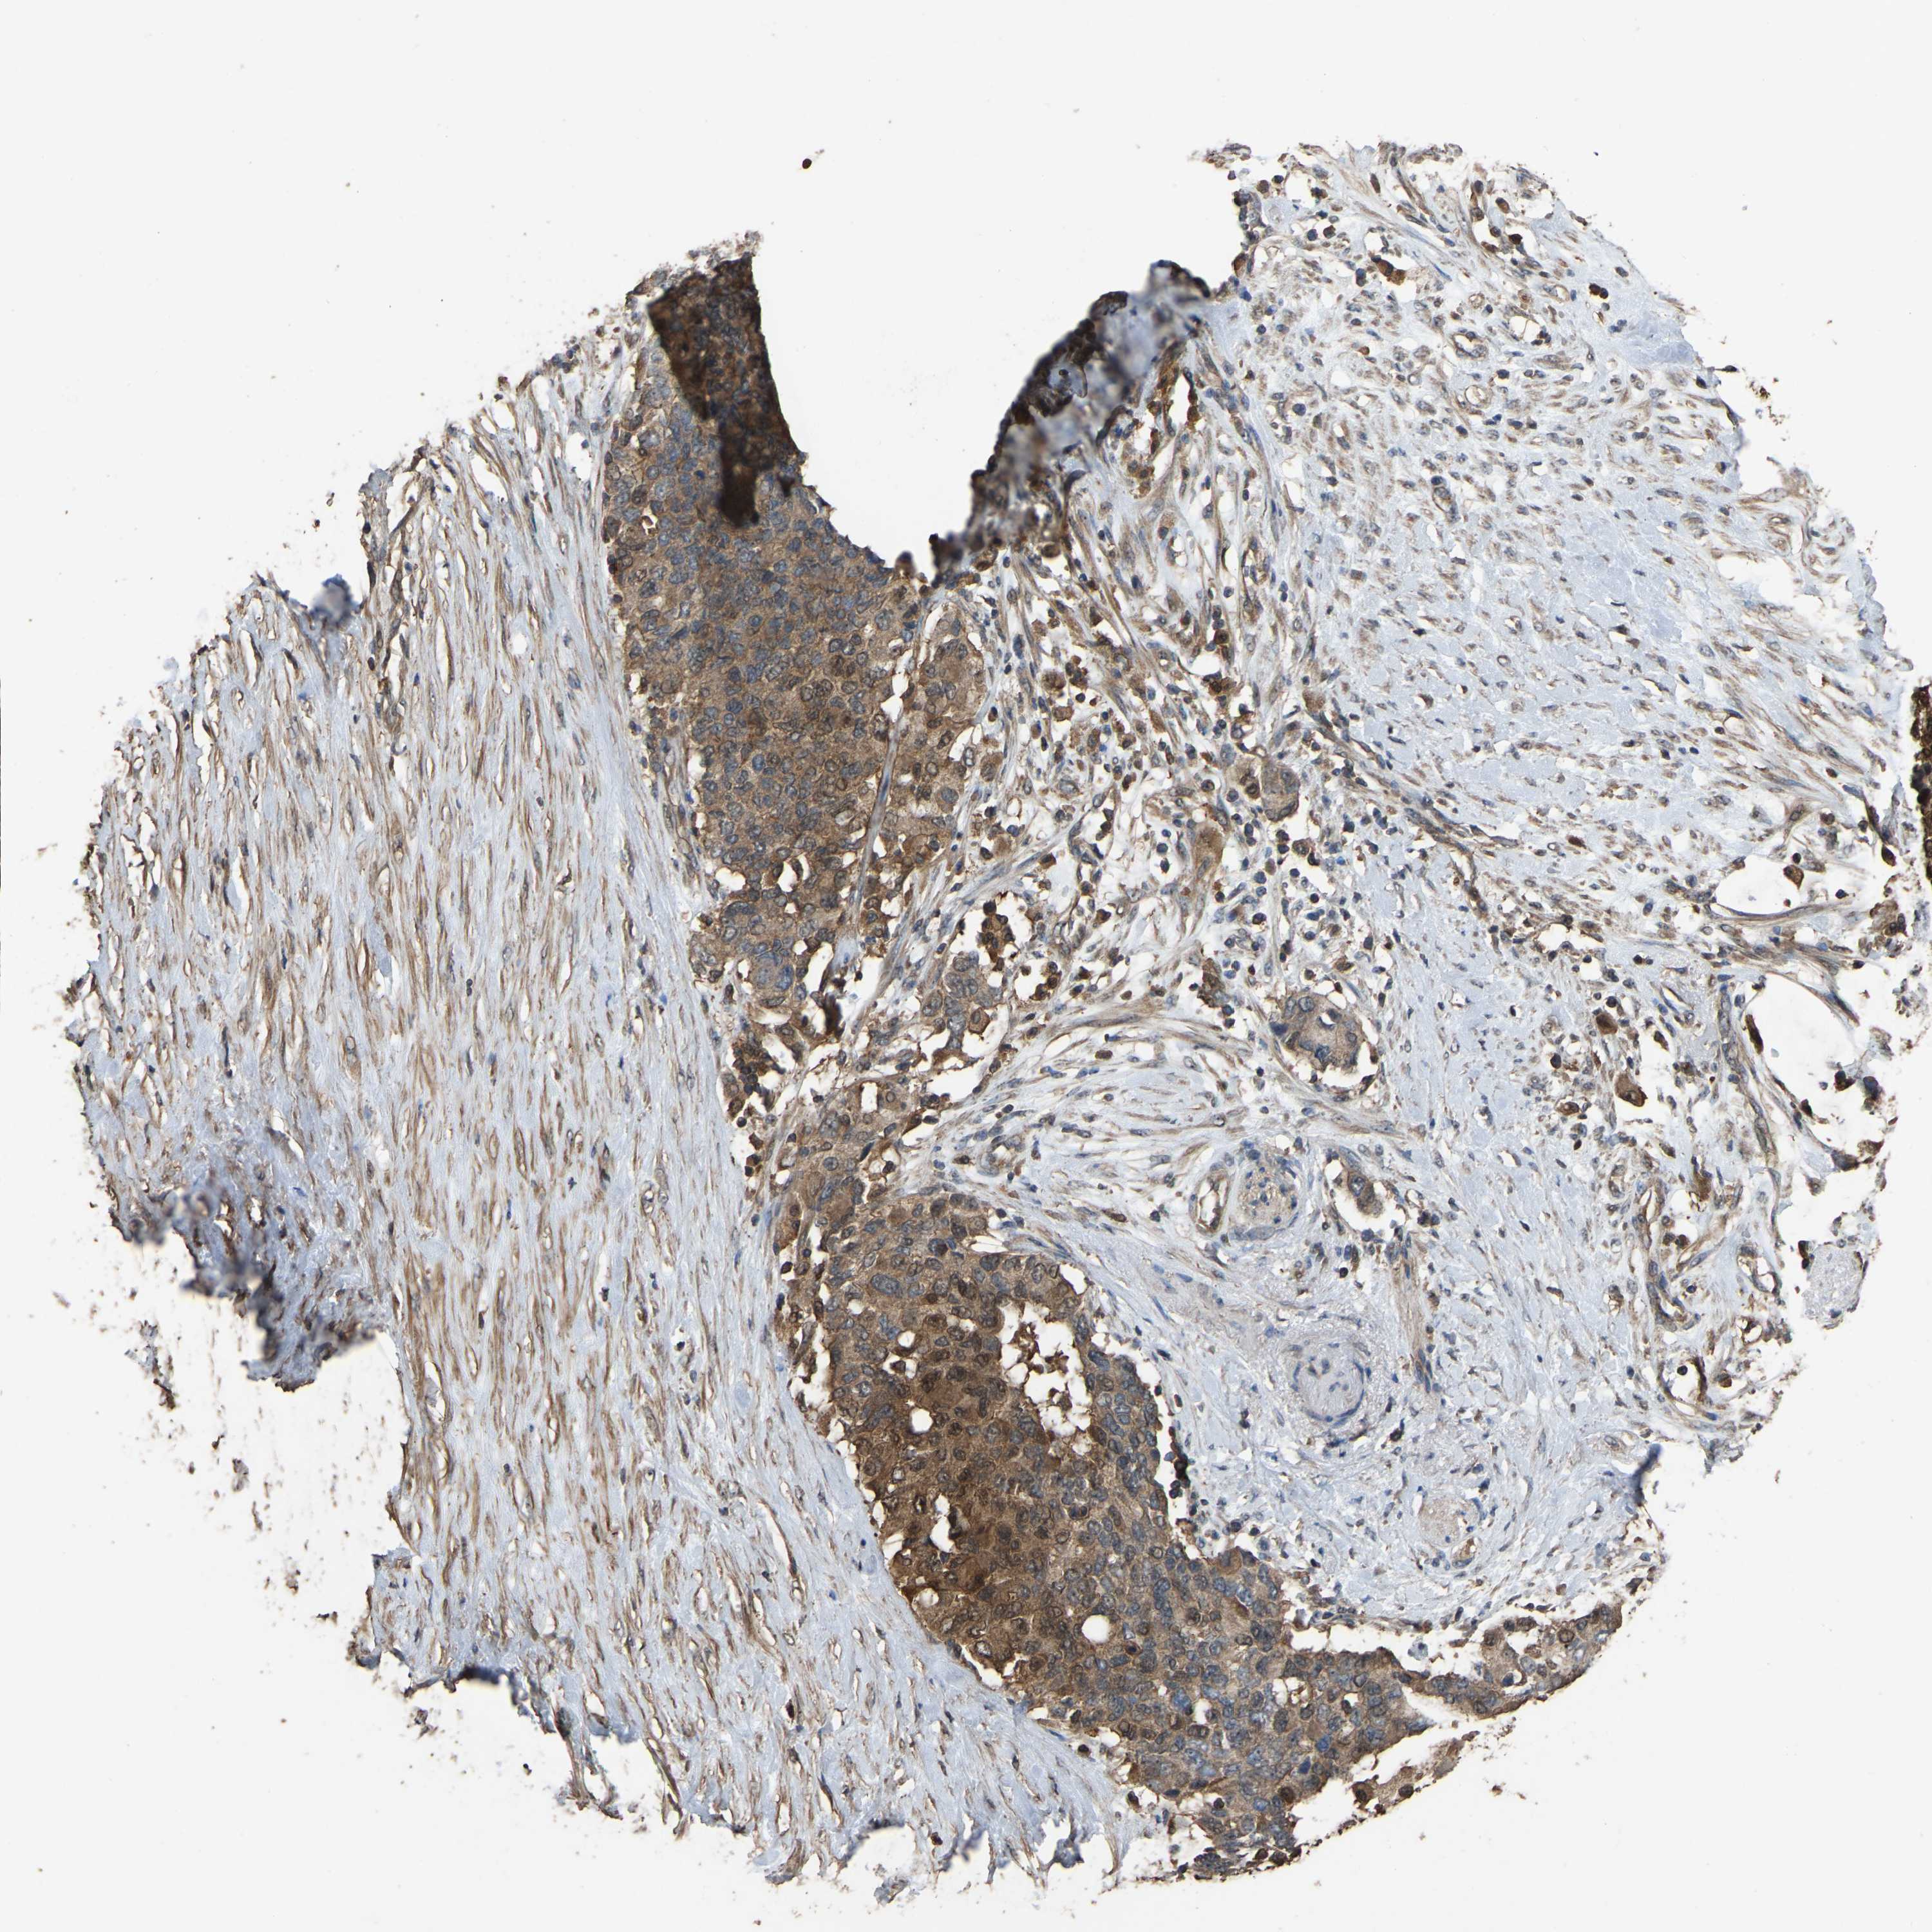

PANCREATIC CANCER - Protein expressioni

A mouse-over function shows sample information and annotation data. Click on an image to view it in a full screen mode. Samples can be filtered based on level of antibody staining by selecting one or several of the following categories: high, medium, low and not detected. The assay and annotation is described here.

Note that samples used for immunohistochemistry by the Human Protein Atlas do not correspond to samples in the TCGA dataset.

Antibody stainingi

Antibody staining in the annotated cell types in the current human tissue is reported as not detected, low, medium, or high, based on conventional immunohistochemistry profiling in selected tissues. This score is based on the combination of the staining intensity and fraction of stained cells.

Each image is clickable and will lead to virtual microscopy that enables deeper exploration of all samples and also displays staining intensity scores, fraction scores and subcellular localization as well as patient and tissue information for each sample.

Antibody HPA018840

Antibody HPA018909

Antibody CAB002684

Staining

High

Medium

Low

Not detected

Intensity

Strong

Moderate

Weak

Negative

Quantity

>75%

75%-25%

<25%

None

Location

Nuclear

Cytoplasmic/membranous

Cytoplasmic/membranous,nuclear

Adenocarcinoma, NOS

Adenocarcinoma, metastatic, NOS